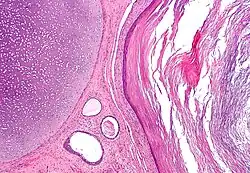

Micrograph of a teratoma, a tumour that characteristically has tissue from all three germ layers. The image shows tissue derived from the mesoderm (immature cartilage - left-upper corner of image), endoderm (gastrointestinal glands - center-bottom of image) and ectoderm (epidermis - right of image). H&E stain.